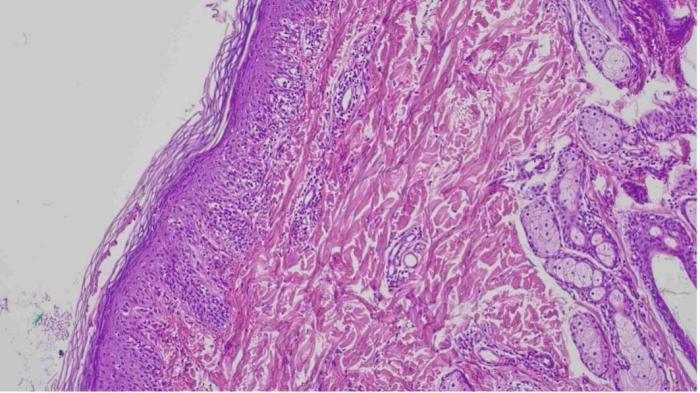

Tras 10 días de tratamiento, las lesiones mostraron una mejoría leve, por lo que se decidió obtener múltiples muestras mediante biopsia cutánea con trocar de 6 mm. El examen histopatológico evidenció un patrón inflamatorio compuesto principalmente por linfocitos que afectaba la unión dermoepidérmica, con vacuolización ocasional y apoptosis de queratinocitos, especialmente a nivel basal, compatible con una dermatitis de la unión citotóxica (Figura 4 y 5).

Los hallazgos histopatológicos típicos de esta patología consisten en una dermatitis de interfase linfocítica rica en células, caracterizada por un infiltrado dérmico prominente en banda (patrón liquenoide), compuesto principalmente por linfocitos y células plasmáticas, y acompañado de incontinencia pigmentaria (ver Figura 4 y 5).